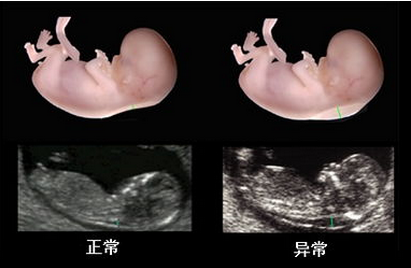

在线咨询随着彩超系统的突飞猛进,系统彩超营运而生,深受孕妈的青睐。系统彩超可以对胎儿进行智力筛查和排畸检查,掌握胎儿生长发育状况,为了能够达到检测的较佳效果,做系统彩超需要注意什么?

贵阳和谐阳光医院引进系统彩超,能够实时获取三维图像,超越了传统超声的限制,能立体、实时地显示人体器官的三维立体结构,为临床超声诊断提供更丰富的影像信息。

1、高端产检设备:贵阳和谐阳光医院引进的系统彩超对孕妇产前检查、各种疾病的诊断,有着现今其他超声无可替代的优越性,是目前上较为先进、科学的超声诊断仪器。